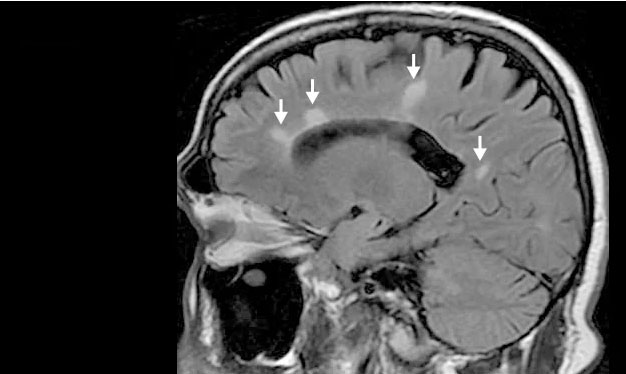

MRI :

که می تواند نواحی ام اس (ضایعات) مغز و نخاع شما را نشان دهد. برای برجسته کردن ضایعاتی که نشان می دهد بیماری شما در مرحله فعال است ، ممکن است از یک ماده حاجب تزریق وریدی کنید.

در اکثر افراد مبتلا به ام اس عود کننده-عودکننده ، تشخیص کاملاً ساده و مبتنی بر الگویی از علائم سازگار با بیماری است که توسط اسکن های تصویربرداری مغز ، مانند MRI تأیید می شود.

تشخیص اس ام می تواند در افرادی که علائم غیرمعمول یا بیماری پیش رونده دارند دشوارتر باشد. در این موارد ، آزمایش بیشتر با تجزیه و تحلیل مایع نخاعی ، پتانسیل برانگیخته و تصویربرداری اضافی ممکن است لازم باشد.